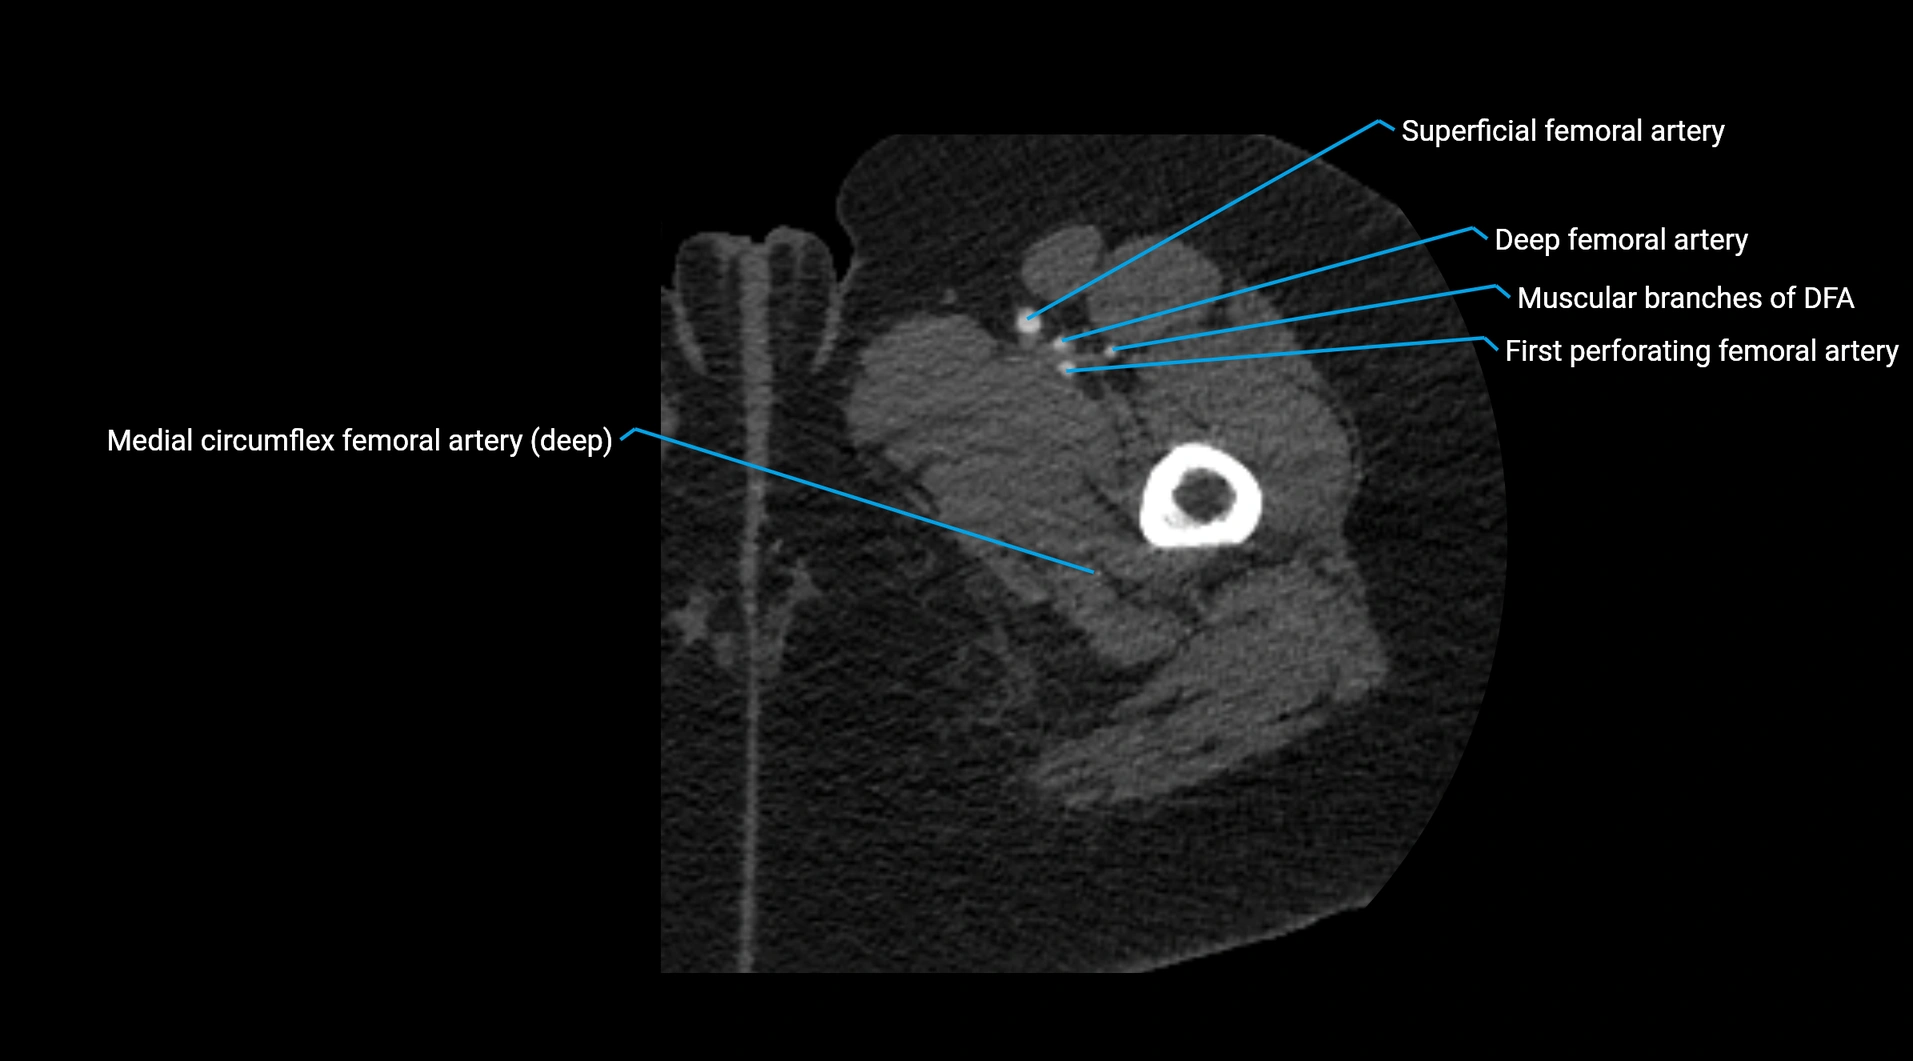

Contrast-enhanced CT (CTA):

• Gold standard for abdominal aortic imaging

• Provides excellent detail of lumen, wall, aneurysm, thrombus, and branch vessels

• Multiplanar and 3D reconstructions help in aneurysm measurement, stent graft planning, and dissection evaluation